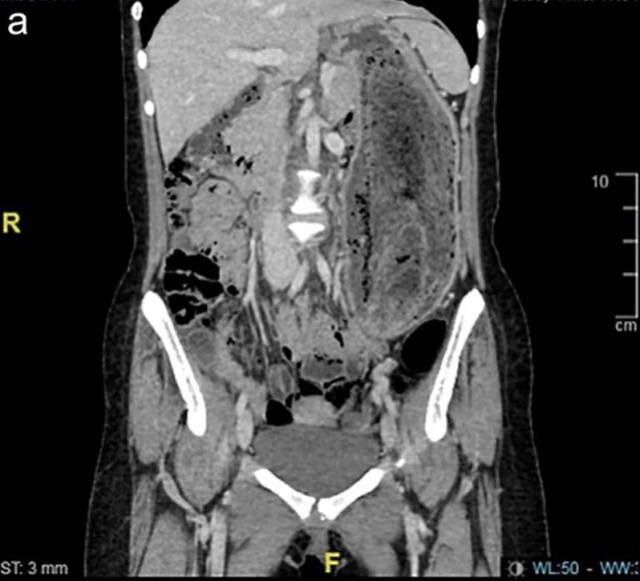

Do kích thước của khối tóc, việc loại bỏ bằng phương pháp nội soi là không thể nên nữ bệnh nhân đã phải trải qua phẫu thuật mở dưới gây mê toàn thân.

Búi tóc lớn được lấy ra cẩn thận và vẫn còn nguyên vẹn. Và sau 3 giờ đồng hồ, dị vật đã được lấy ra an toàn.